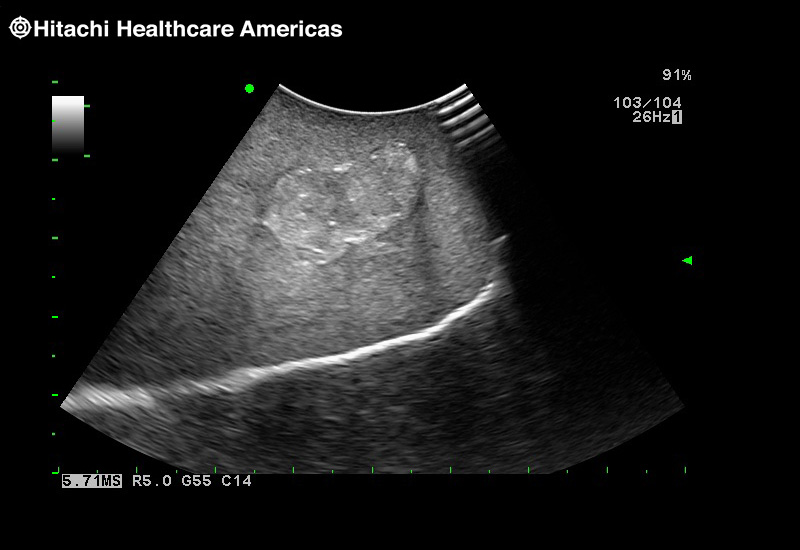

Superior guidance for all applications

Fujifilm Healthcare Americas is committed to designing tools that help surgeons navigate inside the human body and provide the necessary information to immediately make critical surgical decisions.

Fujifilm Healthcare's dedication to Surgeons provides outstanding ultrasound technology, professional support and the specialized tools necessary to best perform comprehensive real-time ultrasound imaging in Breast Surgery, General Surgery, Laparoscopic Surgery, Neurosurgery, Robotic Surgery and Surgical Oncology.